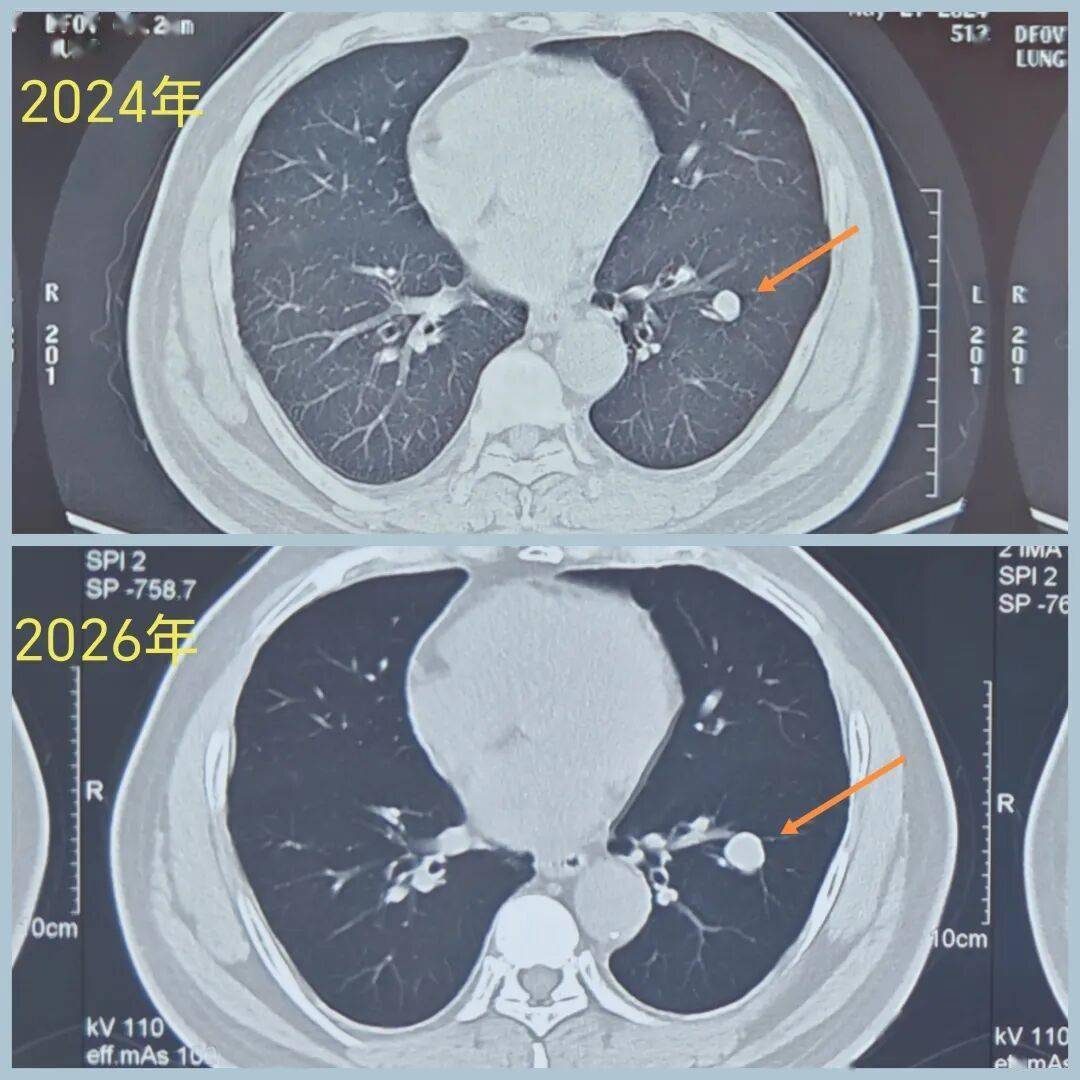

男性,40+岁,发现左下叶实性结节5年

患者诉结节刚发现时为0.8cm,形态像良性,给予定期复查

后结节 逐渐增大

2026年3月CT示病变1.6cm

虽然病变像良性,但一直在增大,不能除外肺癌,因此有手术指征。

(再早片子无法追溯,只能对比24年的片子。)

术前CT示:左肺下叶基底段实性结节,大小1.6cm,边界清,有浅分叶,内部密度不均,有点状高密度。看形态确实像良性。